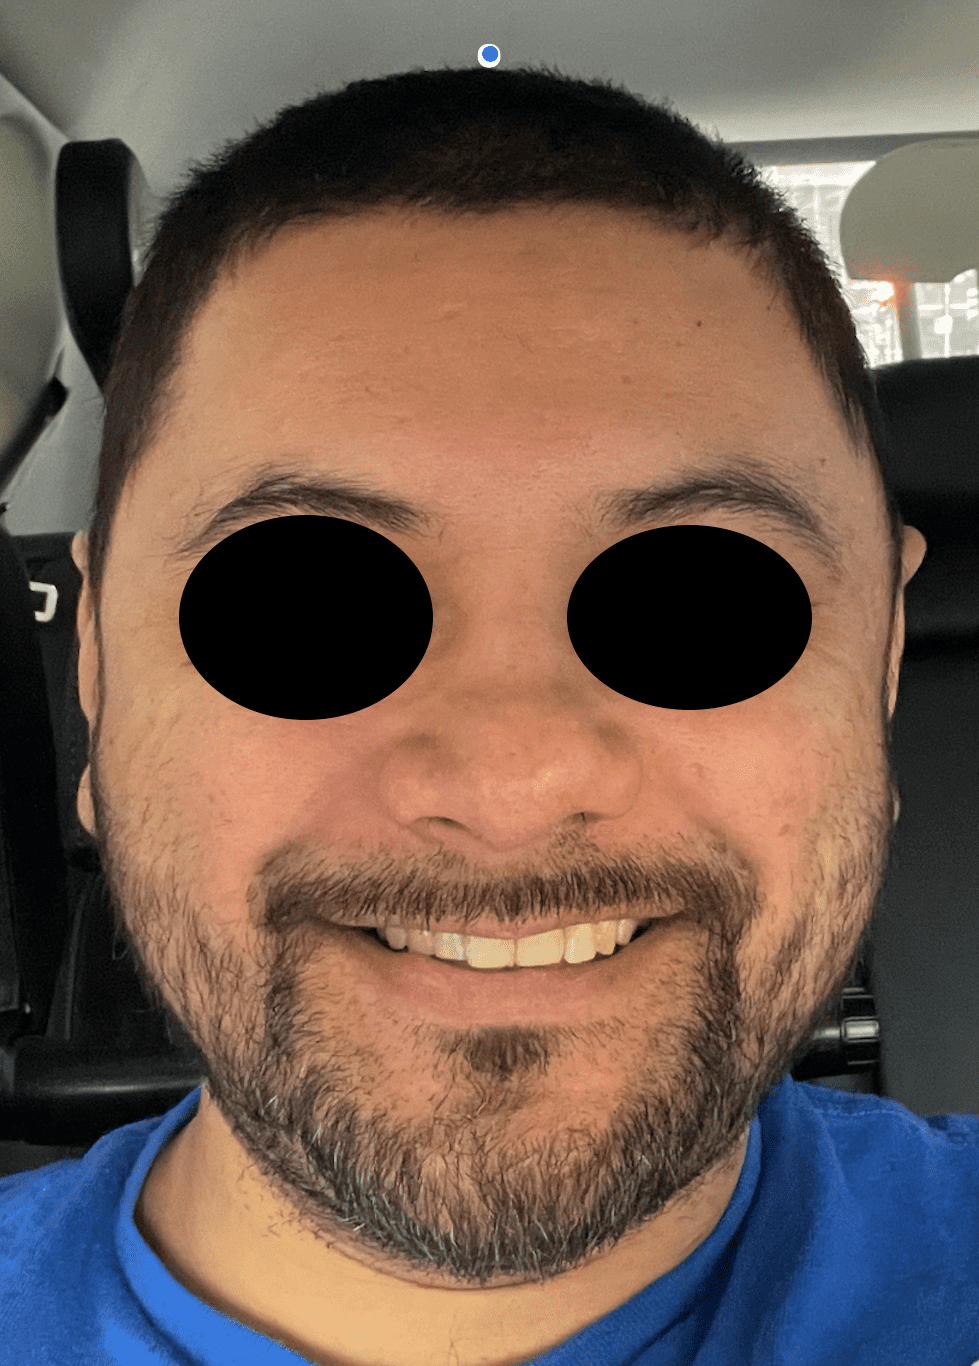

Young male seeking reduction of his convex sides of his head.

Head width reduction by posterior temporal muscle reduction through hidden postauricular incisions behind the ears.

Young male seeking reduction of his convex sides of his head.

Head width reduction by posterior temporal muscle reduction through hidden postauricular incisions behind the ears.